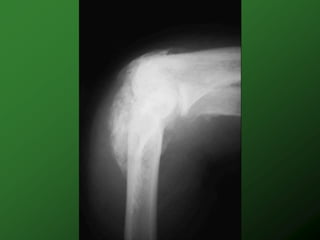

Mechanism Injury

 Flexion

 Hyperextensio

n

 Compression

Mechanism Injury  Flexion  Hyperextensio n  Compression  Rotation